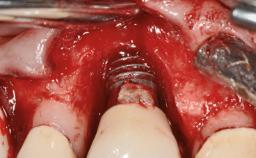

Peripheral Giant-cell Granuloma Associated with Peri-implant Tissues

# of Implants 5

Type of Implants One-Piece

Placement Protocol Early or late implant placement